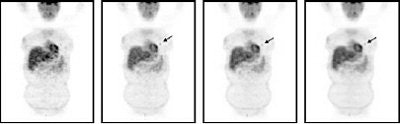

![]() |

| Patient (46-year-old; weight 160 lb) with non-small cell lung cancer. Small focus of increased uptake corresponded to 1.3-cm primary lung cancer. On prospective evaluation, this lesion had been missed on one-minute/bed position images. Reprinted by permission of the Society of Nuclear Medicine from: Halpern BS, et al, Impact of Patient Weight and Emission Scan Duration During on PET/CT Image Quality and Lesion Detectability. J Nucl Med 2004;45:791-801, p.800, Fig. 2. |

They found that one-minute/bed position emission scans were fine for detecting lesions in patients in Category 1, while two-minute/bed position emission scans were sufficient across all weight groups. However, "because four lesions were missed on one-min/bed position scans, such short scan durations should not be used in patients with higher weights," they said.

They concluded that 35 minutes was the maximum imaging time in patients who weighed more than 250 lb. In patients who weighed less than 130 lb, PET/CT scans were obtained within eight minutes. By implementing this weight-based PET/CT protocol at their institution, the authors said they have studied more than 2,000 patients with 14-minute scans.